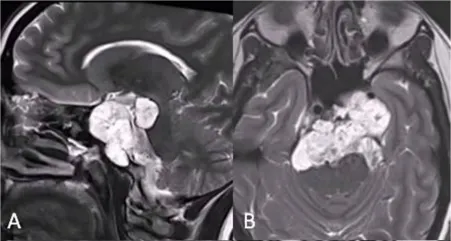

26岁女性,阵发性复视,进行性左外展神经麻痹,MRI显示斜坡巨大脊索瘤,病变浸润性生长,肿瘤延伸浸润至乙状窦(SS)、左侧海绵窦(CS)、下斜坡到脑干脚间池硬膜部分(图A、B)。

该名女士找到INC福教授进行手术,第一期手术,福教授采用联合内镜鼻内入路(EEA)切除硬膜外部分重量,对于硬膜内部分肿瘤采用经颅入路,以降低脑脊液漏和神经血管损伤的风险。

首先,进行内镜鼻内活检,显示典型的脊索瘤。然后,她接受了内镜经鼻入路手术,从硬膜外部分切除到斜坡和海绵窦部分的肿瘤(图C、D)。

2个月后,进行第二次手术,使用右侧mini经岩骨入路切除硬膜内肿瘤。术后MRI显示肿瘤完全切除GTR(图E、F)。术后接受了质子束治疗(PBT)。5个月随访时,她的神经系统检查正常,头面部外观美容效果也非常好。